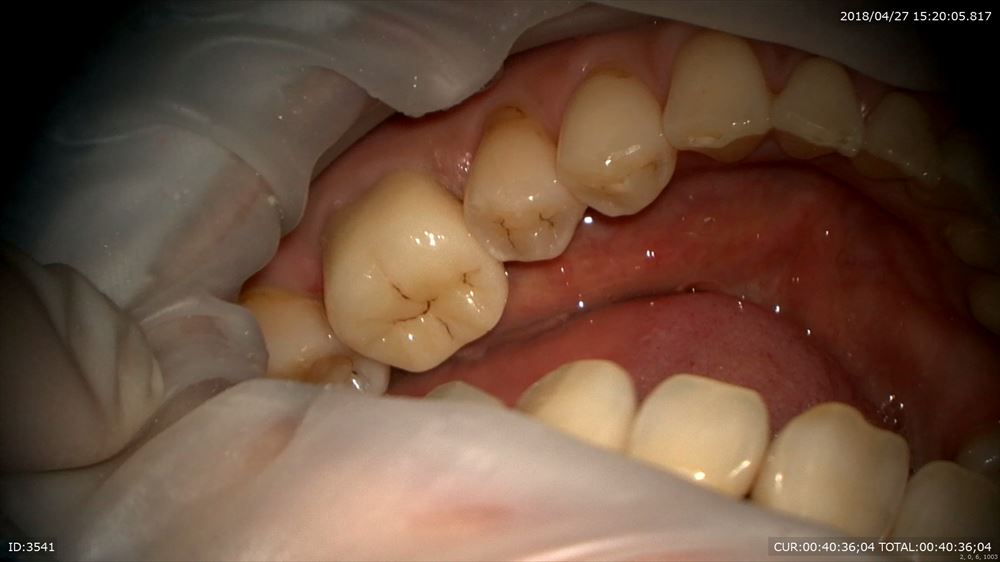

25倍でフィットの確認

スムーズ

これならプラーク付かない!

かみ合わせ調整後。

この様に当院では奥歯にも妥協しない治療を致します。